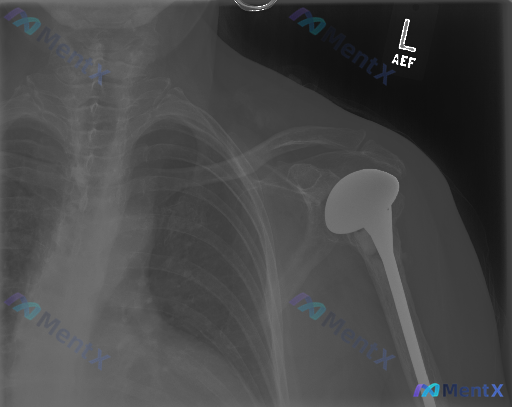

这张左侧肩部X光片,大家觉得是“异常”还是“正常术后改变”?

整理到一张左侧肩部正位X光片及配套的完整分析报告,大家可以先看核心影像信息: - 影像显示左侧肩关节已行肱骨头置换术(半肩置换),可见金属假体占据肱骨近端位置 - 肱骨假体柄位于肱骨髓腔内,假体头与关节盂相对,未见明显假体松动、透亮带或假体周围骨折 - 显影范围内的锁骨、肩峰、喙突及部分肋骨未见明显...